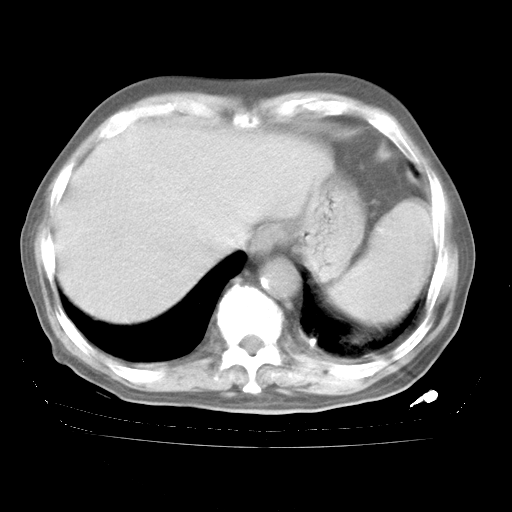

4月28日肺部CT——再次出现类似去年5月9日——透光度降低,“间质性”改变。

4月28日肺部CT——再次出现类似去年5月9日——磨玻璃样、间有“粟粒样”改变。

4月28日肺部CT